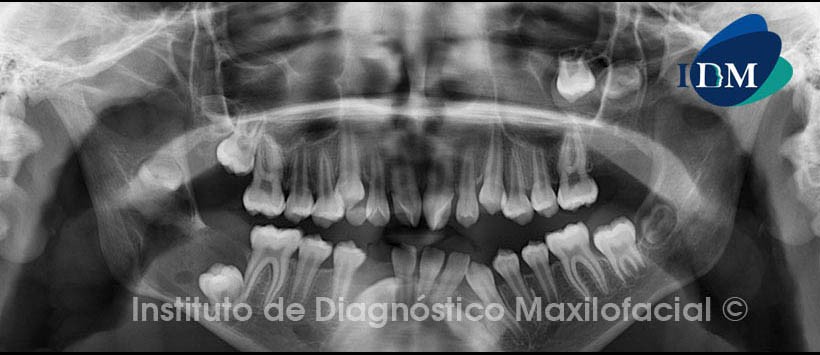

Al estudio tomográfico volumétrico (CBCT) mediante cortes axiales (Fig. 2), reformación panorámica (Fig.3) y reconstrucciones 3D (Fig. 4) apreciamos lesiones isodensas localizadas en el maxilar superior: a nivel de la corona de la pieza 2.8, la misma que se encuentra desplazada cefálicamente.

En el maxilar inferior a nivel coronal de las piezas 3.2 y 4.3, que se encuentra impactada en posición mesioangular, y a nivel del cuerpo y rama mandibular del lado derecho, provocando leve expansión de la tabla ósea lingual y desplazamiento cefálico de la pieza 4.8 así como caudal con aparente impactación de la pieza 4.7.